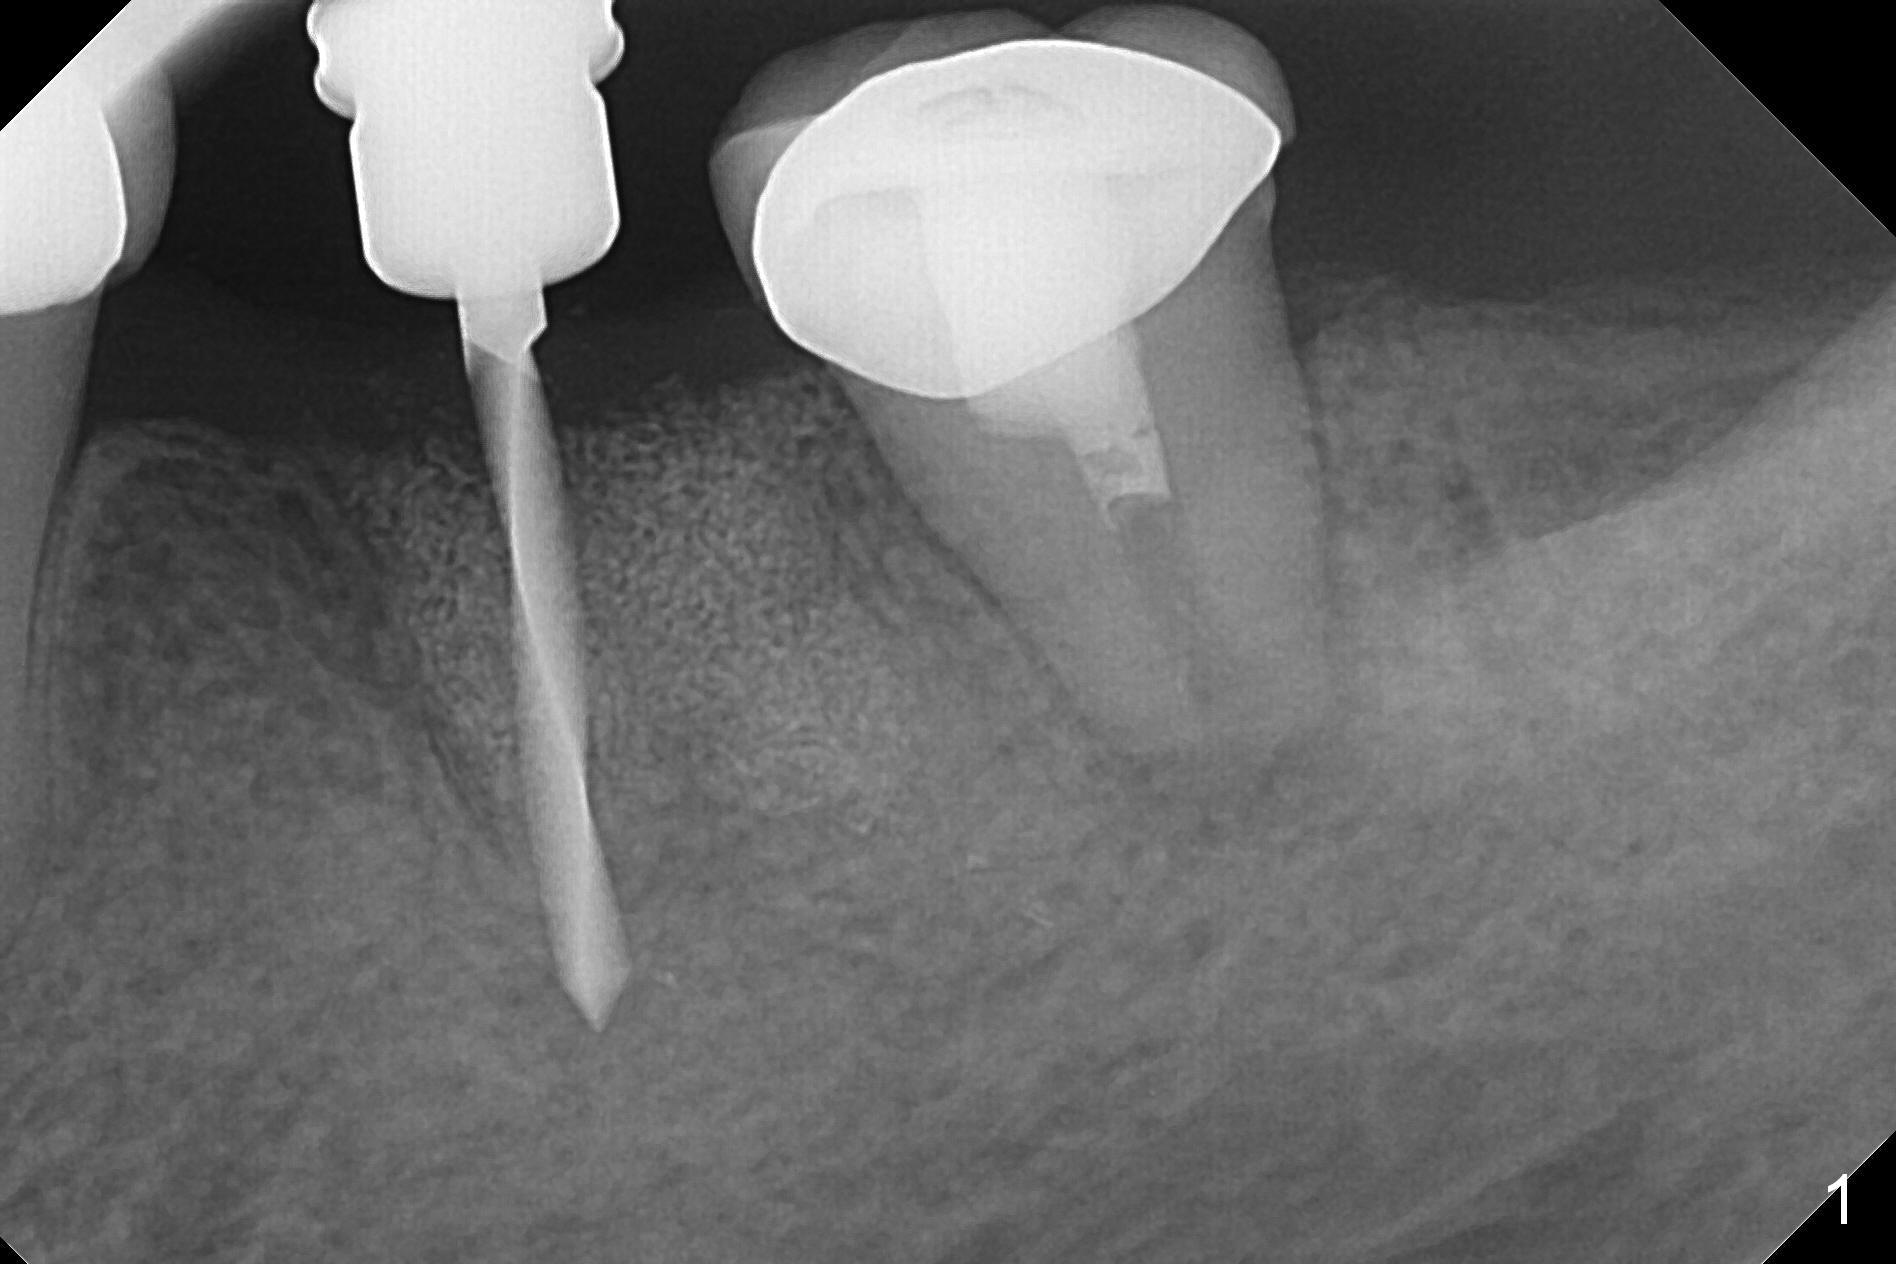

After making a 10 mm incision at the site of #19, #15c blade is used as an osteotome to start bone expansion, followed by Magic Split and Magic Expander (ME, 3 mm in diameter). The depth is approximately the bottom of the mesial socket. The osteotomy beyond the socket has to be done with 1.6 mm pilot drill (Fig.1) in combination of ME. Following ME 4.3 mm and Magic Drill (MD) 3.8 mm for 15 mm (gingival level), a 4.5x11 mm dummy implant is placed with 50 Ncm (Fig.3); the implant looks narrow for the edentulous space. After ME 4.8, MD 4.3 for 13 mm and Final Drill for 15 mm, a 5x11 mm IBS is inserted with >50 Ncm (Fig.3). With 2 more turns of the implant, a 6.5x4(2) mm abutment is placed (Fig.4). Periodontal dressing is applied around the abutment for additional retention. A provisional is fabricated 3 weeks postop. The provisional and abutment are loose 4 months postop (Fig.5). After retightening the abutment, impression is taken for final restoration. There is no bone loss 1 year 3 months post cementation (Fig.6). After use of #100 file (Fig.7), the canal is debrided with #140 file with 1.5 mm shorter in working length with placement of Calcium Hydroxide paste. Pain gets worse post RCT retreatment. There is limited native bone for primary stability when an immediate implant is placed (red dashed line: the superior border of the Inferior Alveolar Canal). Prepare IS regular and extra wide kits and tissue-level implants (>5 mm). Socket preservation may be done instead. If the socket is large and the vein is not so small, prepare PRF. In fact blood drawing fails. When the tooth is extracted, it is sensitive to remove granulation tissue. Socket preservation is done with Vanilla graft at #18 (Fig.8); there is ~3.5 mm bone between the bottom of the single socket and the Inferior Alveolar Canal (red dashed line). The socket at #18 seems to have healed 4 months post extraction (Fig.19), but the bone height appears to have been reduced (compare Fig.10,11). The buccolingual width is also decreased (Fig.12,13). A 4.5 or 5.0x10 mm implant is appropriate for the site (Fig.14). There is no bone loss at #19 (which may be associated with the bone expansion) 1.5 years post cementation (Fig.15). Therefore the osteotomy at #18 will be assisted with bone expanders after 2.2 mm drill.